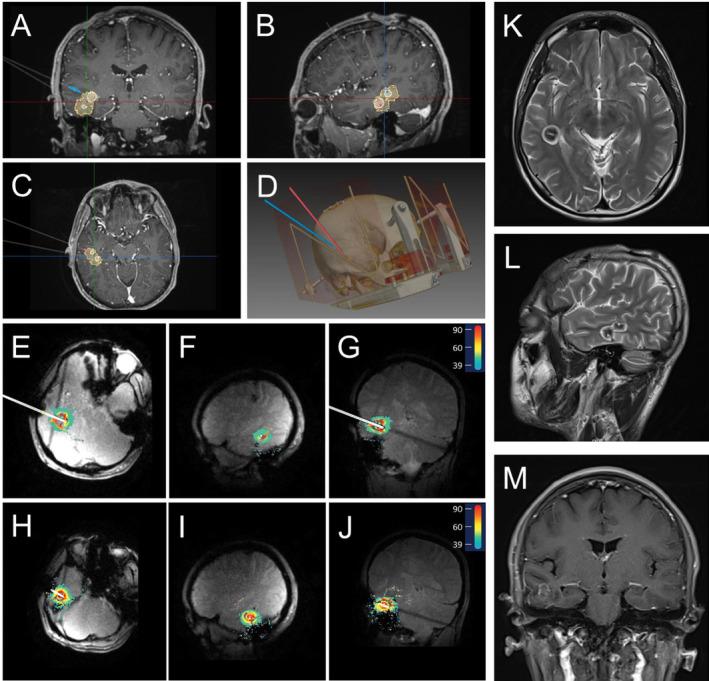

Magnetic resonance-guided laser interstitial thermal therapy (MRgLITT) is a novel tool and a minimally invasive treatment to drug-resistant epilepsy (DRE). The focus of this research was to evaluate the effectiveness and safety of the newly developed dual-wavelength dual-output MRgLITT system LaserRO within two probe trajectories in treating DRE patients.

This is a retrospective analysis conducted at a single center, examining patients with DRE who received treatment with the LaserRO MRgLITT system. The system utilizes a sophisticated laser technology that can be configured as conventional single output for single wavelength or innovative dual outputs for dual wavelengths. The study involved a comprehensive review of patient information, encompassing demographics, seizure history, details related to the surgical parameters, and the subsequent clinical results. Primary outcome was post-operation seizure outcome defined as Engel Scale Class at the end of follow-up time.

This study included a total of eight DRE patients received MRgLITT surgery between August 2022 and October 2023. Out of these, there were four mesial temporal lobe epilepsy (MTLE), three focal cortical dysplasia (FCD), and one cavernous malformation (CM) patients. Within the two probe trajectories, seven patients had single wavelength (980 or 1064 nm) laser treatment and one patient had dual-wavelength (980 and 1064 nm) laser treatment. The median age of the patients was 27 (22-31) years, with a median follow-up period of 9.7 (8.4-12.1) months. The mean BMI was recorded at 20.24 ± 2.95 kg/m, and epilepsy history was 13 ± 6 years. The median intraoperative blood loss was 5 (5-9) mL, operation time was 231 (169-254) minutes, and length of stay (LOS) was 3 (3-5) days. The mean ablation volume ratio was 96.52% ± 3.67%. In terms of outcomes, over a median follow-up time of 9.7 (range 8.4-12.1) months, there were two patients got Engel I, five patients got seizure-free, and one patient decreased 75% seizure. Importantly, no serious complications following the procedures occurred.

The preliminary results indicate that the MRgLITT procedure, which operates dual-output laser with single or dual wavelengths (980/1064 nm) within the two trajectories, is both effective and safe as a minimally invasive approach for different types of DRE patients.